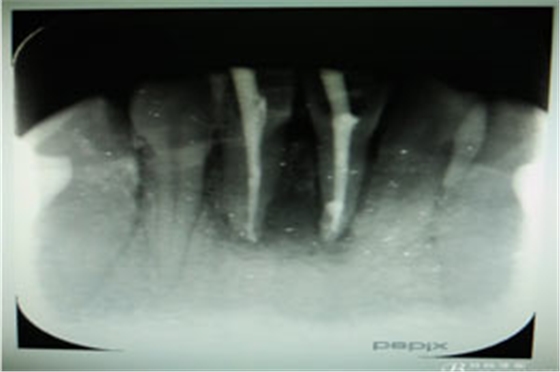

圖2.術(shù)前的根尖片影像、31根管治療已做,欠填少許。31、41根尖有橢圓形陰影,未見明顯骨白線。